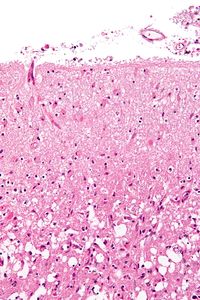

Micrograph showing cortical pseudolaminar necrosis, a finding seen in strokes on medical imaging and at autopsy. H&E-LFB stain.

Micrograph of the superficial cerebral cortex showing neuron loss and reactive astrocytes in a person that suffered a stroke. H&E-LFB stain.